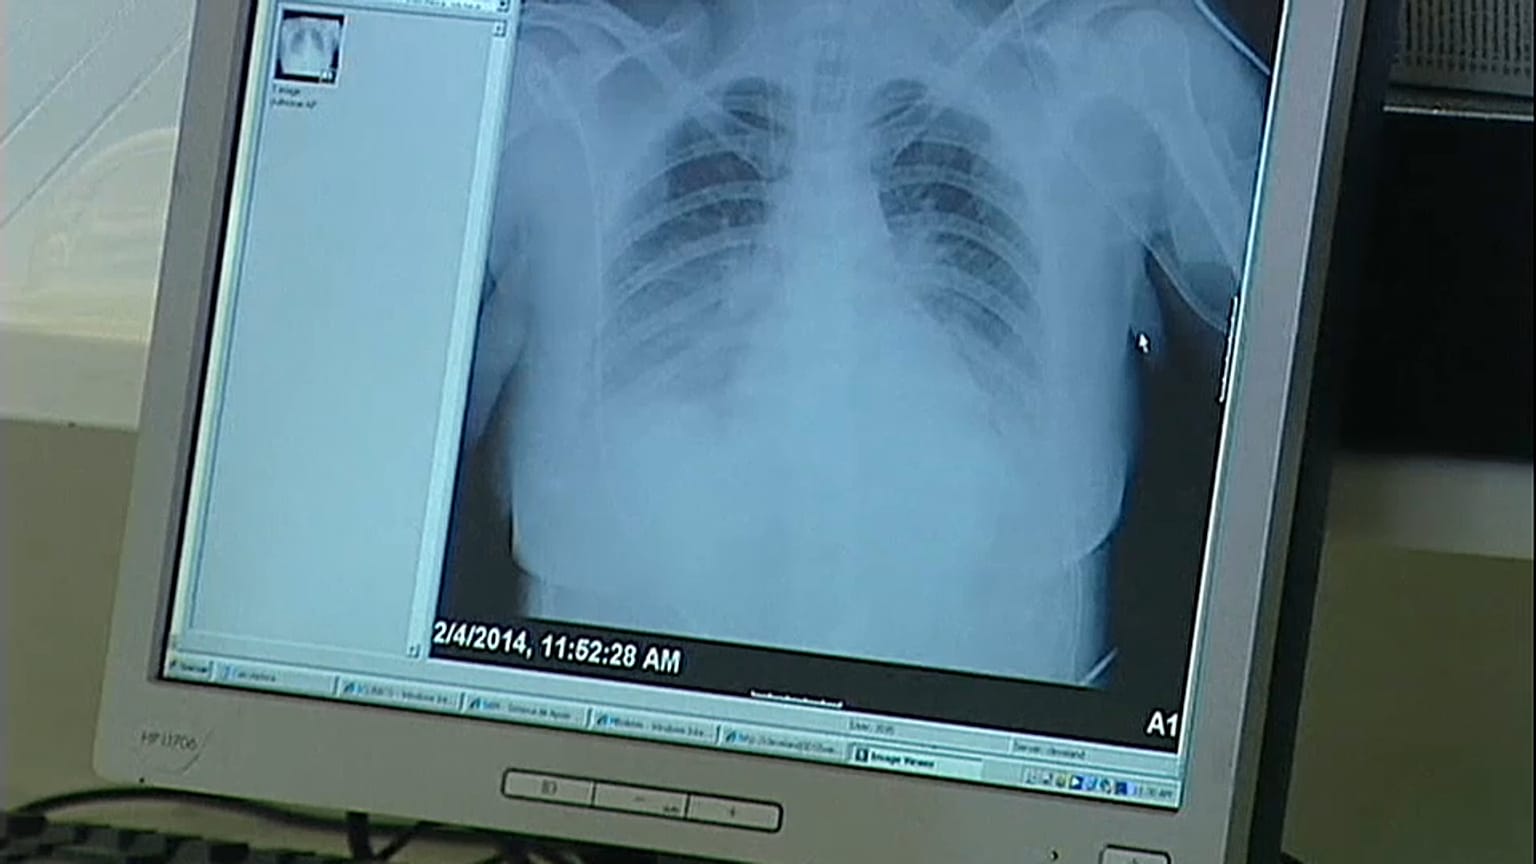

A probabilidade de sobrevivência de pacientes com cancro de pulmão aumenta quando o tratamento associa ativadores do sistema imunulógico à quimioterapia, segundo um estudo publicado no New England Journal of Medicine

A probabilidade de sobrevivência de pacientes com cancro de pulmão aumenta quando o tratamento associa medicamentos ativadores do sistema imunulógico à quimioterapia. Esta é a conclusão de um estudo científico publicado no New England Journal of Medicine, conduzidos por Leena Ghandi, diretora do programa de oncologia toráxica no Perlmutter Cancer Center, da Universidade de Nova Iorque.

O cancro de pulmão é a principal causa de morte por cancro no mundo, causando 1,7 milhão de mortes por ano.